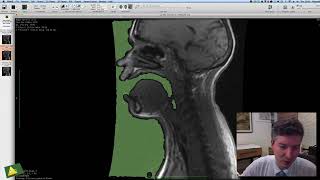

Reconstrução 3D no OsiriX: Volume Rendering básico, Crop, Presets e remoção de ossos.

Inscreva-se no Canal Ver Todas as AulasReconstrução 3D no OsiriX: Volume Rendering básico, Crop, Presets e remoção de ossos.